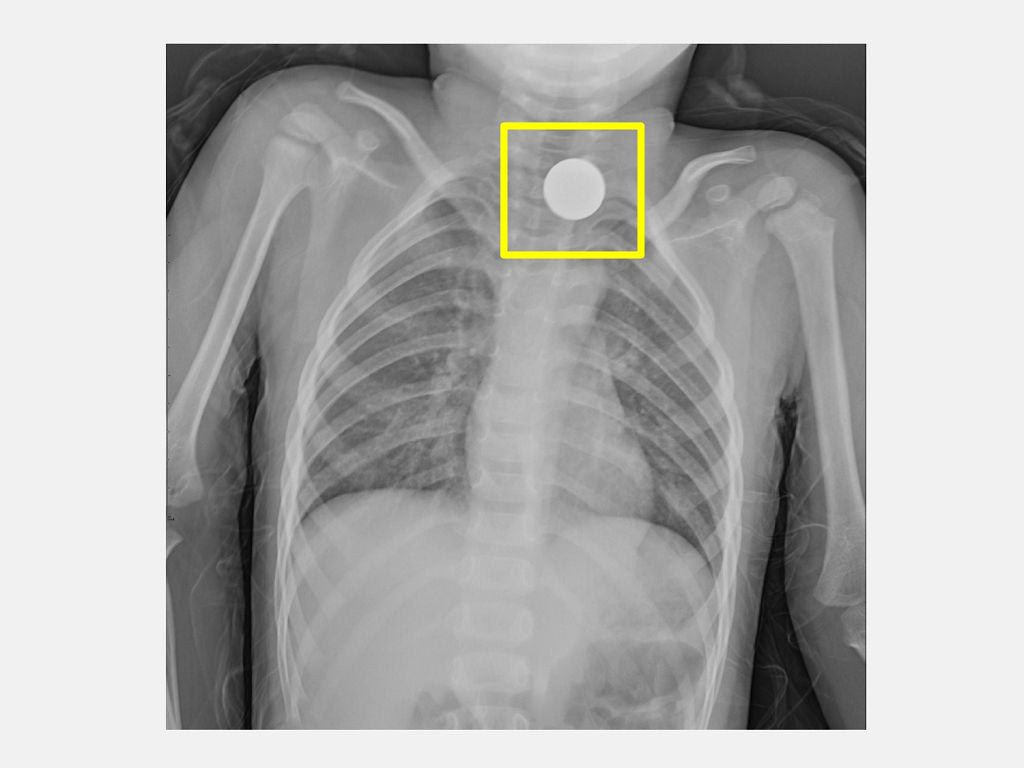

一位3歲小男孩因為疑似吞入異物,被家屬送到仁愛長庚合作聯盟醫院急診室,江鴻逸醫師經過病史與理學檢查發現,小男孩並無呼吸窘迫情形,症狀是喉嚨痛和吞嚥不適,無皮下氣腫,亦無喘鳴呼吸音,前後照胸部X光顯示在食道處有一個環狀扁平異物,診斷為小兒食道異物。江鴻逸醫師立即會診小兒科曾文禹醫師,安排緊急全身麻醉腸胃鏡異物夾取術,前後歷經2小時順利取出一元硬幣,讓家長放下心中的大石。